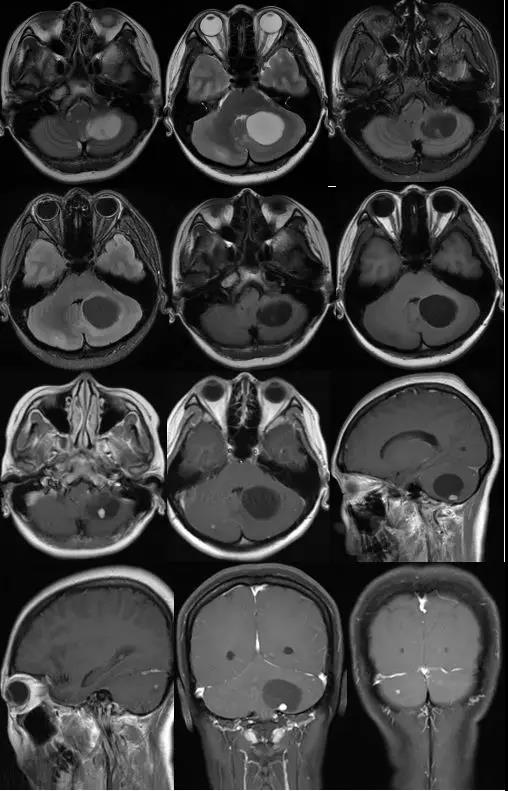

胶质瘤是最常见的原发性脑肿瘤,该病发病机制不明,预后较差,手术切除后容易复发,是神经外科医师倍感棘手的疾病。MDT是脑胶质瘤标准的诊疗模式。河南省人民医院脑肿瘤M...